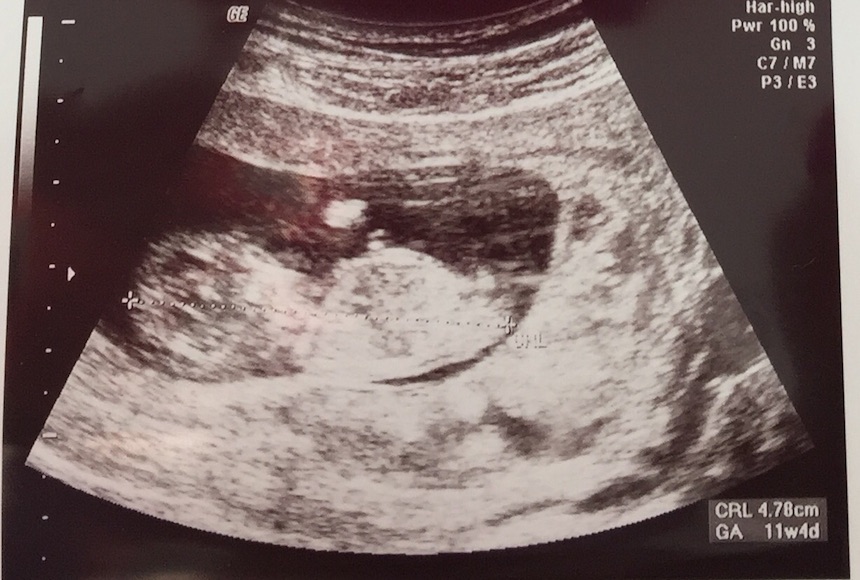

This is my BF's scan at 11w4d. I cant quite find the nub. I think I see 2 nubs LOL! Boy or girl? Please share your thoughts!

Technically too early and not a clear pic, but boy guess.